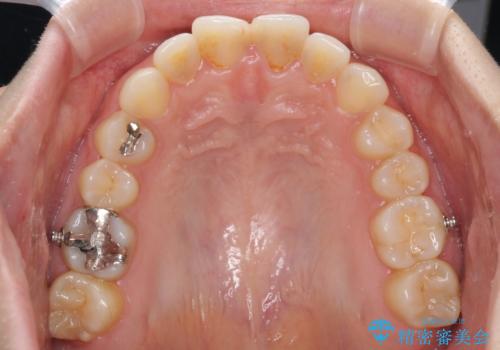

- 以前の矯正治療の後戻りを気にして来院された患者様です。

下顎前歯にデコボコがあるため、ワイヤー矯正により改善することとしました。

もう少しデコボコを改善したかったのですが、ご本人の希望もあり、装置を除去しました。

後戻りを防止するため、舌側を細いワイヤーによる保定を行いました。